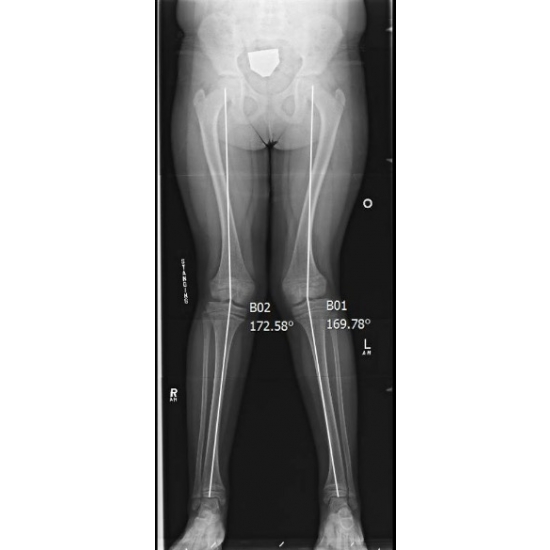

| The Kneediest Puzzle: Chronic Joint Pain With A Surprising Angle In A Young Girl - Page #3 | |||